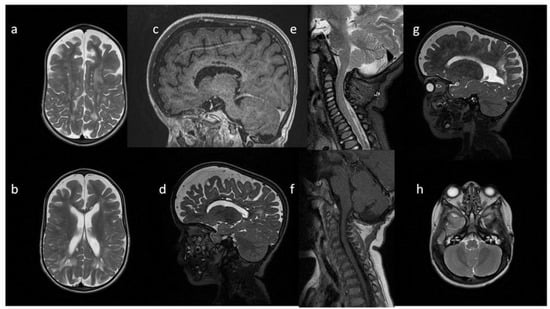

| Patient No | 1 | 2 | 3 | 4 | 5 | |

|---|---|---|---|---|---|---|

| age at exam | 4 mo | 3 yo | 1 y 2 mo | 1 y 11 mo | 3 y 2 mo | 14 yo |

| radiological imaging | ||||||

| WM signal abnormalities | + | + | + | |||

| areas of delayed myelination | + | + | + | + | + | |

| enlarged perivascular spaces | + | + | + | + | ||

| narrow corpus callosum | + | +/− | + | + | ||

| prominent ventricular system | +/− | + | +/− | + | + | |

| arachnoid cyst | + | + | ||||

| optic nerve sheath enlargement | + | + | ||||

| J-shaped sella turcica | + | + | + | +/− | + | +/− |

| craniocervical junction distortion | + | +/− | + | + | ||

| posterior fossa horns | + | + | + | + | ||

| fluid effusion temporal bone | + | + | + | + | +/− | |

| closed sagittal suture | + | + | + | |||

| vertebral bodies deformity | + | + | ||||

| intervertebral disc anomalies | + | + | ||||